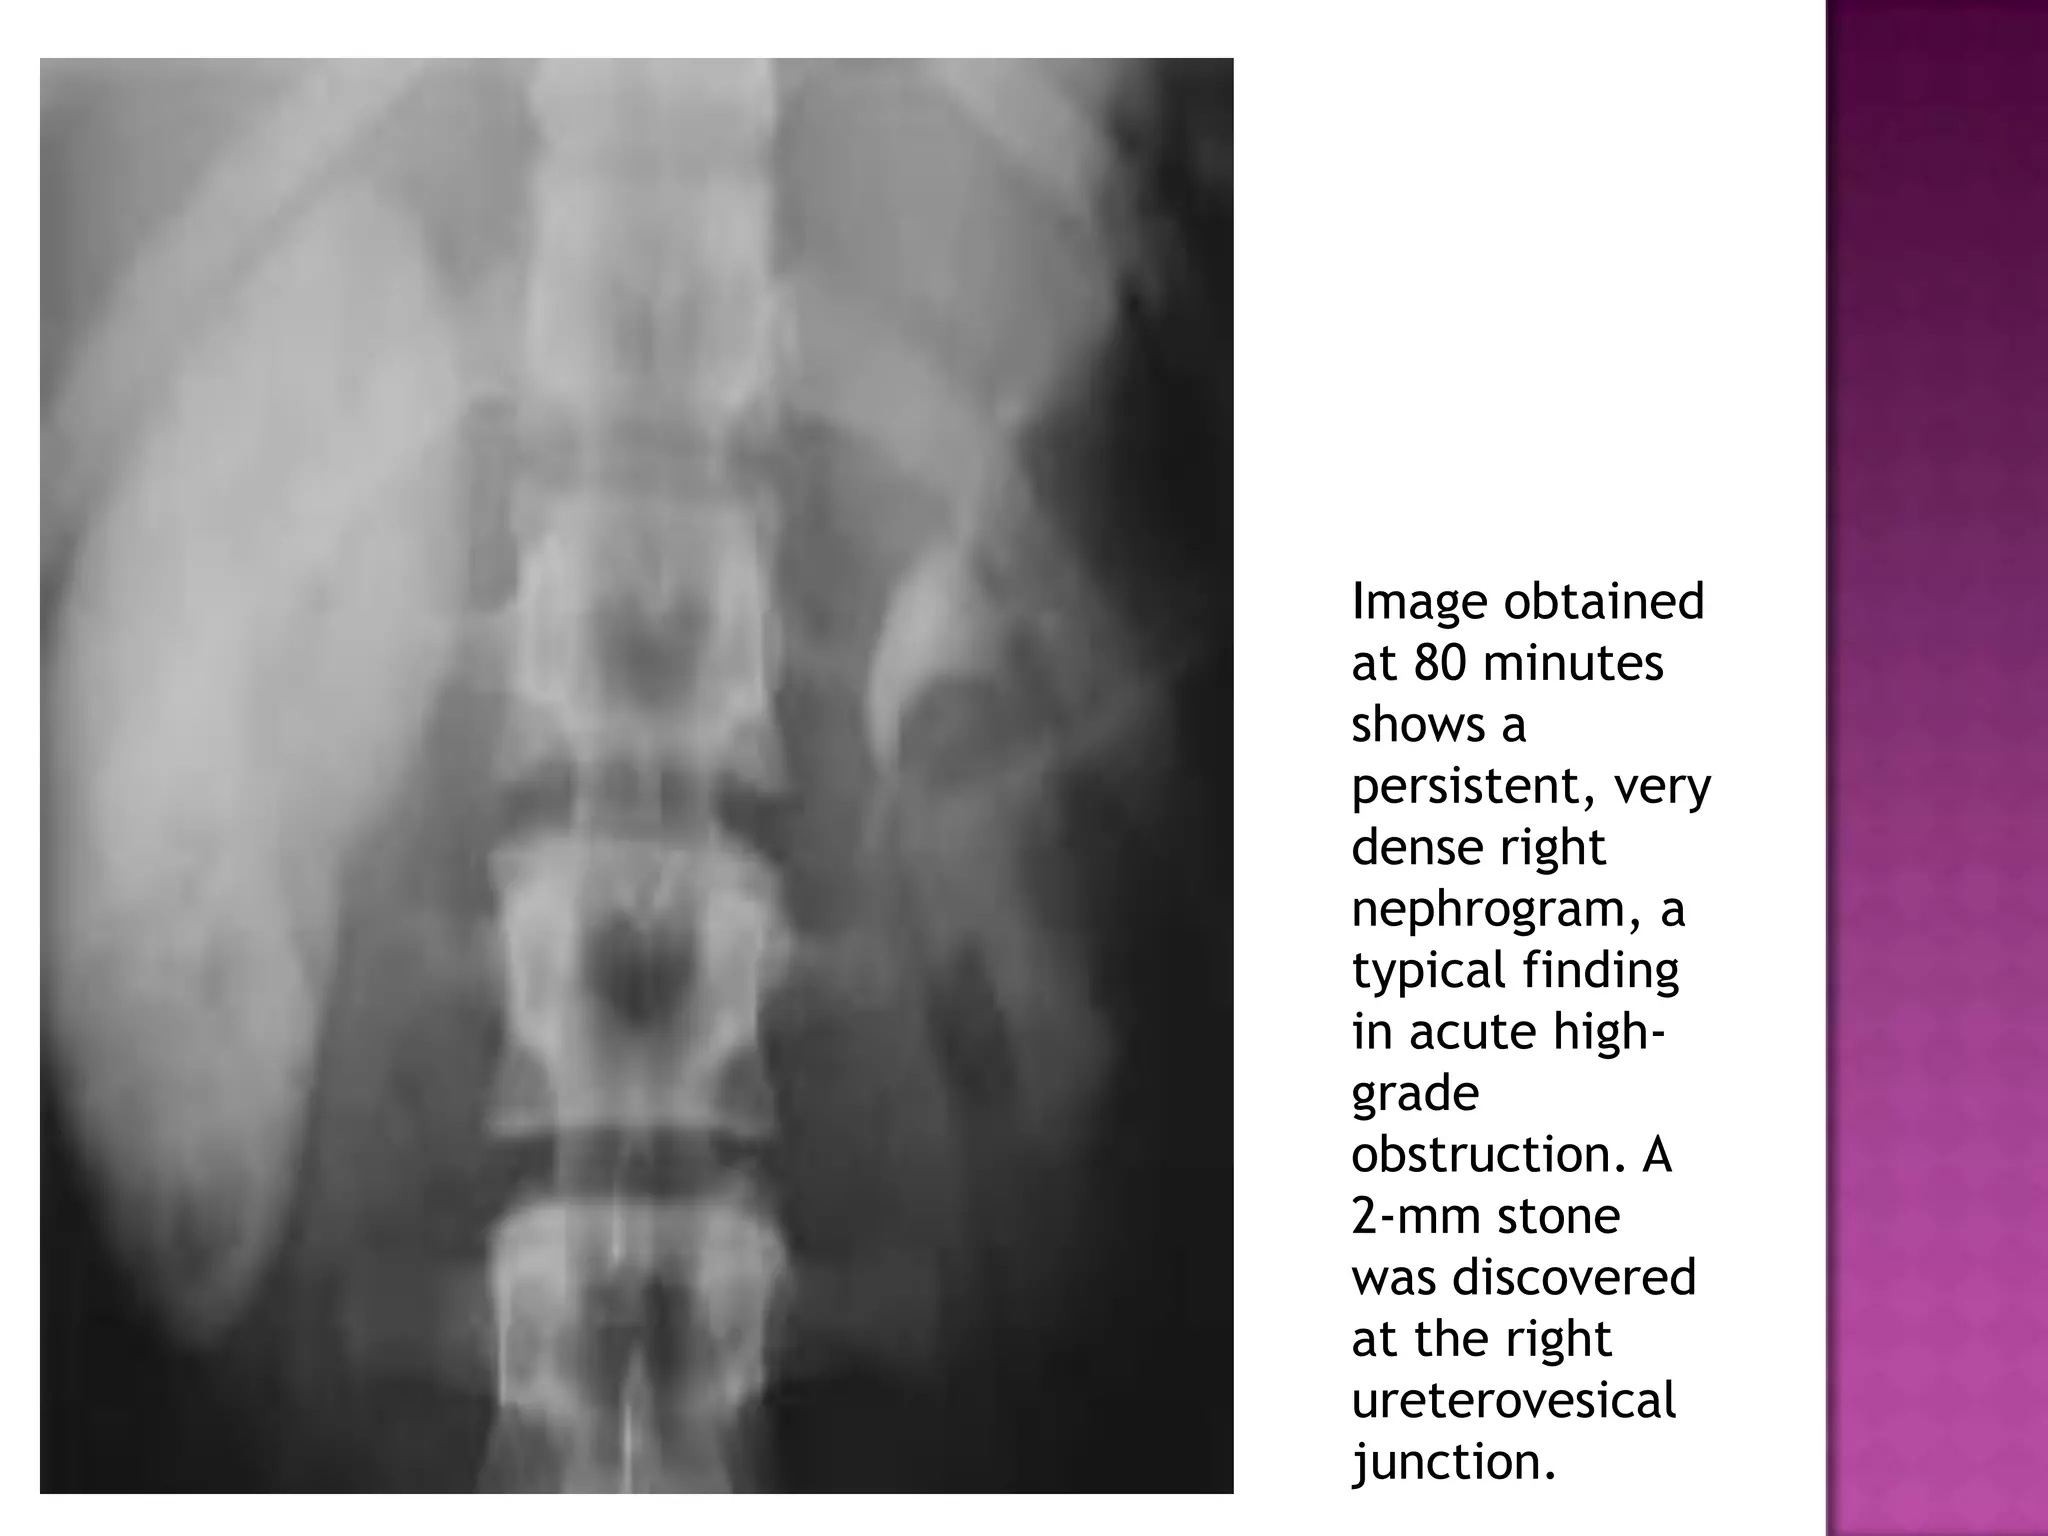

Image obtained

at 80 minutes

shows a

persistent, very

dense right

nephrogram, a

typical finding

in acute high-

grade

obstruction. A

2-mm stone

was discovered

at the right

ureterovesical

junction.

Image obtained at 80minutes shows a persistent, very dense right nephrogram, a typical finding in acute high- grade obstruction. A 2-mm stone was discovered at the right ureterovesical junction.